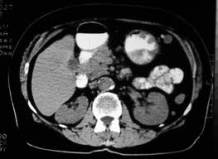

During surgery, the surgeon is often necessary to know the details of the internal structure of the patient to avoid the mistake of blindly pursuing surgery. It uses software that allows you to view real-time visual models of internal organs during surgery, as shown in Figure 1. These models come in 2 types: 2D models and 3D models.

Figure 1. Snapshot tomography

The most commonly used 2D models include photographs of the patient and MRI scans (magnetic resonance imaging) or CT (computed tomography).